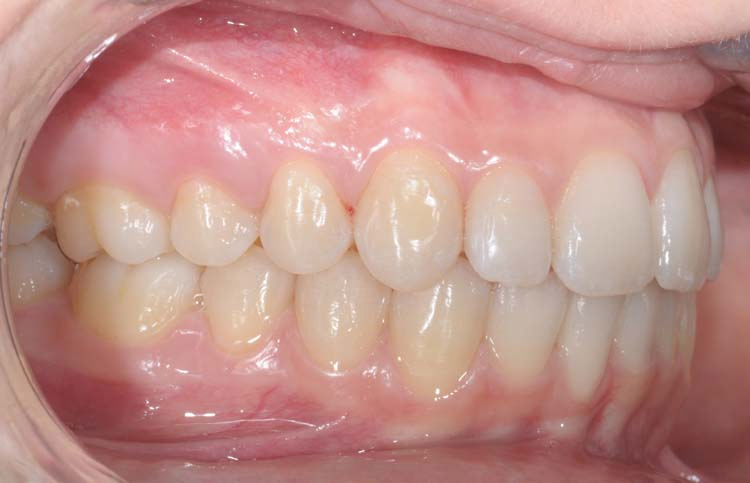

Caso clinico 1

Caso clinico 2

Caso clinico 3

Caso clinico 4

Caso clinico 5

Caso clinico 6